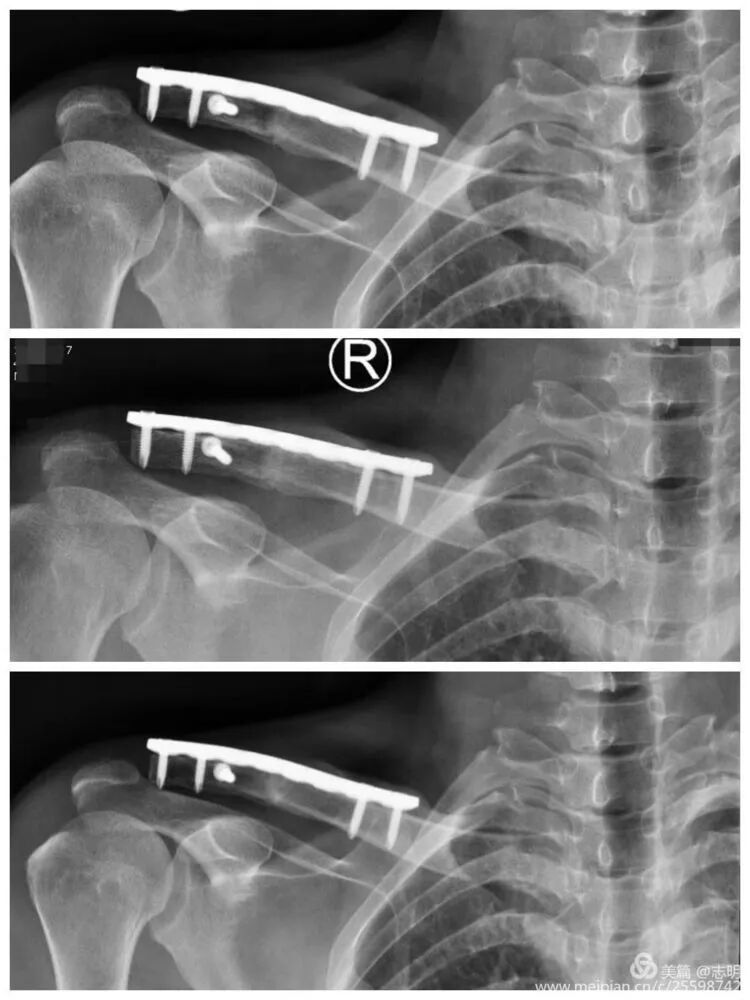

(Post-fixation X-ray showing the plate and screws in place). -

(Another post-fixation X-ray).